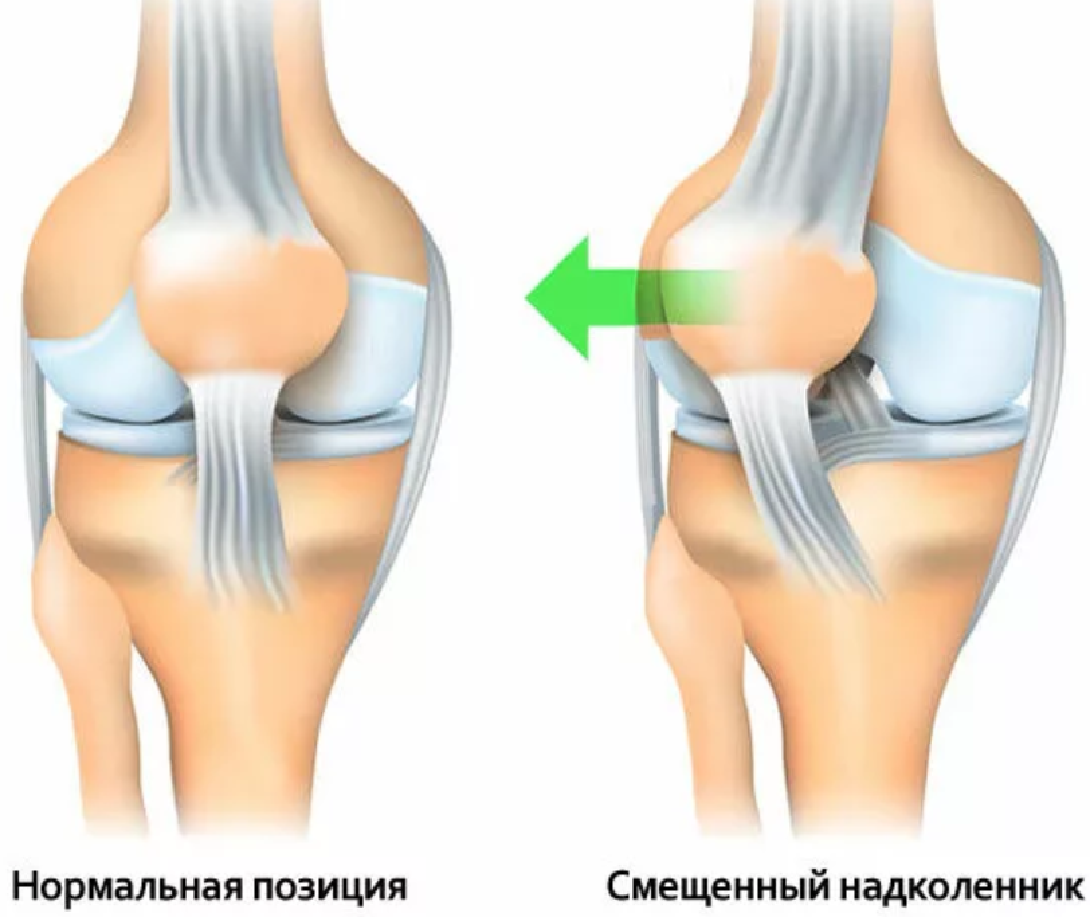

Причины и лечение травм коленного сустава